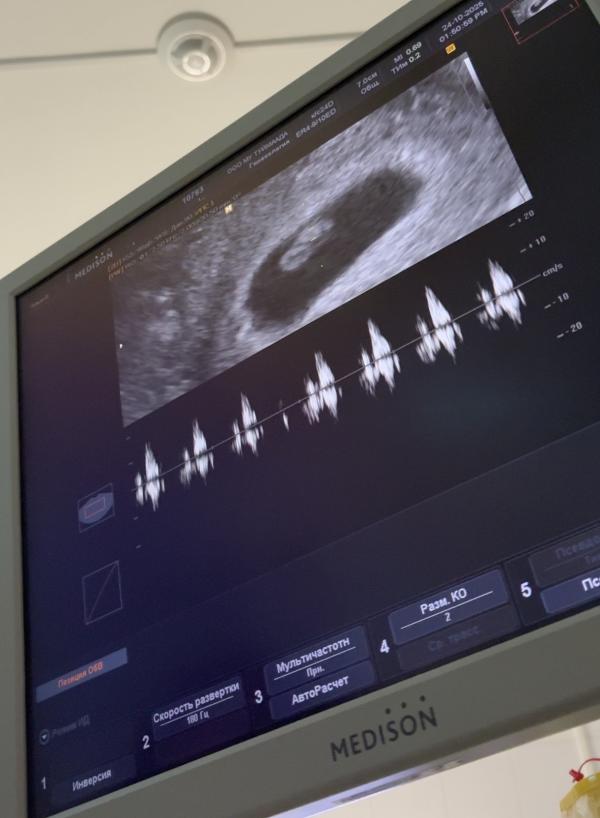

Наша бусинка🫶🏻сердцебиение есть,гематома рассосалась слава богу🙏🏻